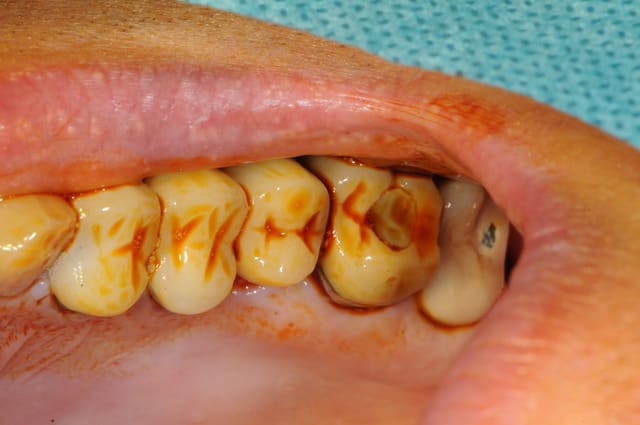

mise à jour et aménagement tissulaire type Palacci

modification des collets et des bords libres

prise empreinte

piliers

couronnes...